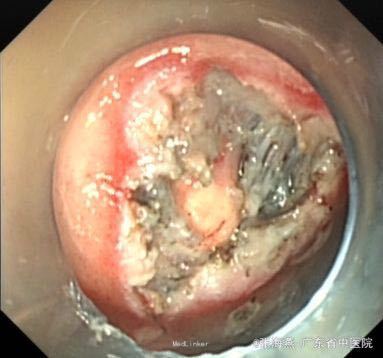

诊断:1.胃底间质瘤(ESD术后);2、慢性胃炎;3、高血压病2级;4、颈椎退行性变。 治疗:治疗上,行ESD术切除胃底肿物,术后予明可欣静滴预防感染,潘妥洛克静滴抑酸护胃,铝镁加混悬液口服保护胃粘膜,以及补液营养支持治疗。术后病理提示:符合胃肠道间质瘤(低级别,无风险);经治疗后,患者无特殊不适,予出院。

随访:ESD术后3月随访,患者无上腹部疼痛发作。 讨论:患者胃底间质瘤已完整切除,属低级别、无风险,就无需服用格列卫,嘱患者定期复查胃镜。